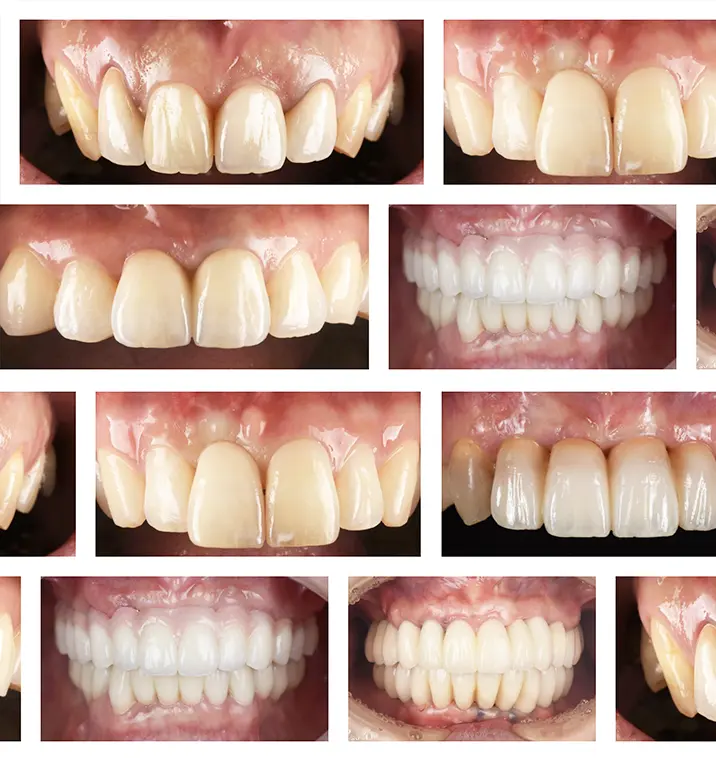

症例紹介

当院のインプラント症例をご紹介します

当院の多様な

インプラント症例を

ぜひご覧ください

当院では、インプラント治療を行う医院選びのご参考となるよう、様々なインプラント症例を紹介しています。大阪市でインプラント治療をご検討の方は、地下鉄四ツ橋駅・心斎橋駅直結のなかやま歯科まで、お気軽にご相談ください。